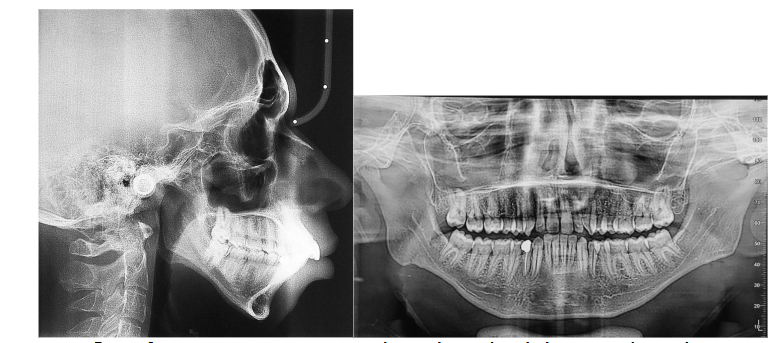

• Panoramic radiograph: The panoramic radiograph revealed a complete dentition with no signs of alveolar bone loss. The mandibular condyles showed normal morphology, with no clinical or radiographic signs of temporomandibular joint dysfunction. A restoration and a root canal treatment were observed on tooth 44.

• Lateral cephalometric radiograph: Cephalometric analysis showed features of posterior mandibular rotation, with GoGn/SN = 46° and FMA = 43°. Steiner and Tweed cephalometric measurements confirmed a skeletal Class II pattern, with pro-alveolar upper incisors and retro-alveolar lower incisors.